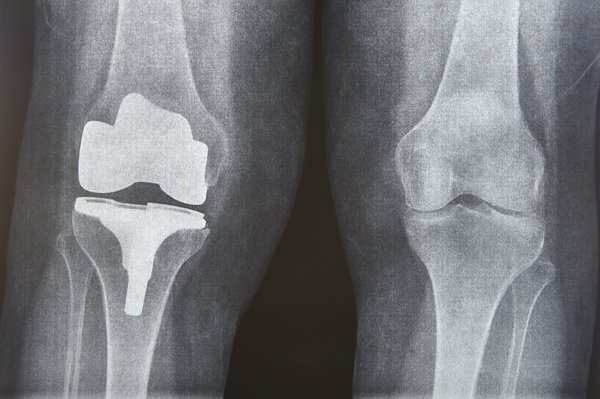

L’arthrose est la résultante d’une dégradation progressive du cartilage qui recouvre les extrémités des os au sein de l’articulation. Cette détérioration peut être accélérée par divers facteurs tels que des déséquilibres hormonaux, l’hérédité, ou encore un surpoids imposant une pression excessive sur les articulations. En outre, des blessures antérieures ou une sollicitation répétée d’une articulation particulière lors d’activités professionnelles ou sportives peuvent également être responsables.

Quant aux symptômes, ils varient selon le stade de la maladie. Dans ses premiers temps, l’arthrose peut se manifester par une douleur sourde après un effort, souvent soulagée par le repos. Cependant, à mesure que la maladie progresse, les douleurs articulaires peuvent devenir plus vives, constantes et perturber le sommeil. La perte de l’autonomie est une crainte légitime puisque la mobilité peut être réduite, rendant les activités quotidiennes plus ardues. Par ailleurs, un gonflement de l’articulation touchée et une diminution de sa flexibilité sont également des indices révélateurs. Vous pouvez visiter www.focm.net pour mieux comprendre cette pathologie.